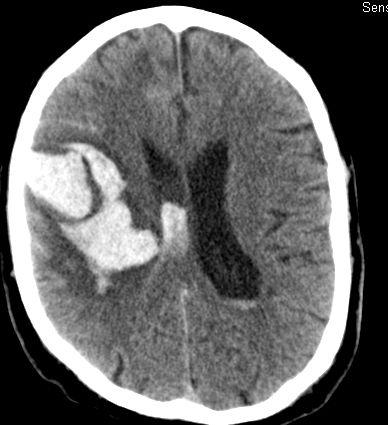

Als diagnostische Maßnahme wird in der Regel ein craniales Computertomogramm (CCT) durchgeführt. Intrazerebrale Blutungen lassen sich mit dieser Methode sicher diagnostizieren.

Je nach Lokalisation und Ausdehnung der Blutung und in Abhängigkeit vom klinischen Zustand des Patienten muss entschieden werden, ob eine chirurgische Intervention notwendig ist. In diesem Falle wird über eine Eröffnung der Schädeldecke die Blutung in mikrochirurgischer Technik entfernt.

Bild einer intracerebralen Blutung nach OP.

Bild einer intracerebralen Blutung vor OP.